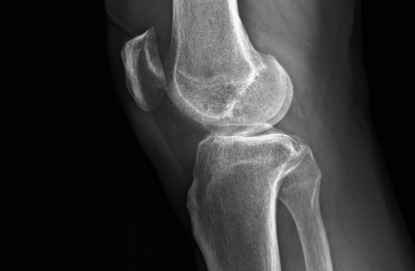

半膝人工關節置換術術前X光(膝蓋側面) -